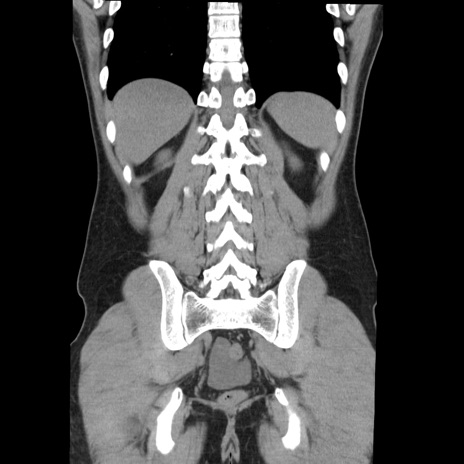

症例36(冠状断像)

【症例】20歳代 男性

【主訴】心窩部痛

【現病歴】今朝より上腹部痛あり。一旦軽快していたが再度出現したため救急要請。昨日夕に白身の魚を含む刺身を食べた。

【身体所見】BP 136/89mmHg、HR 74/min、BT 37.0℃、腹部:膨満、軟、心窩部に圧痛あり。反跳痛なし、筋性防御なし、腸雑音やや亢進あり。

【データ】WBC 17700、CRP 0.48